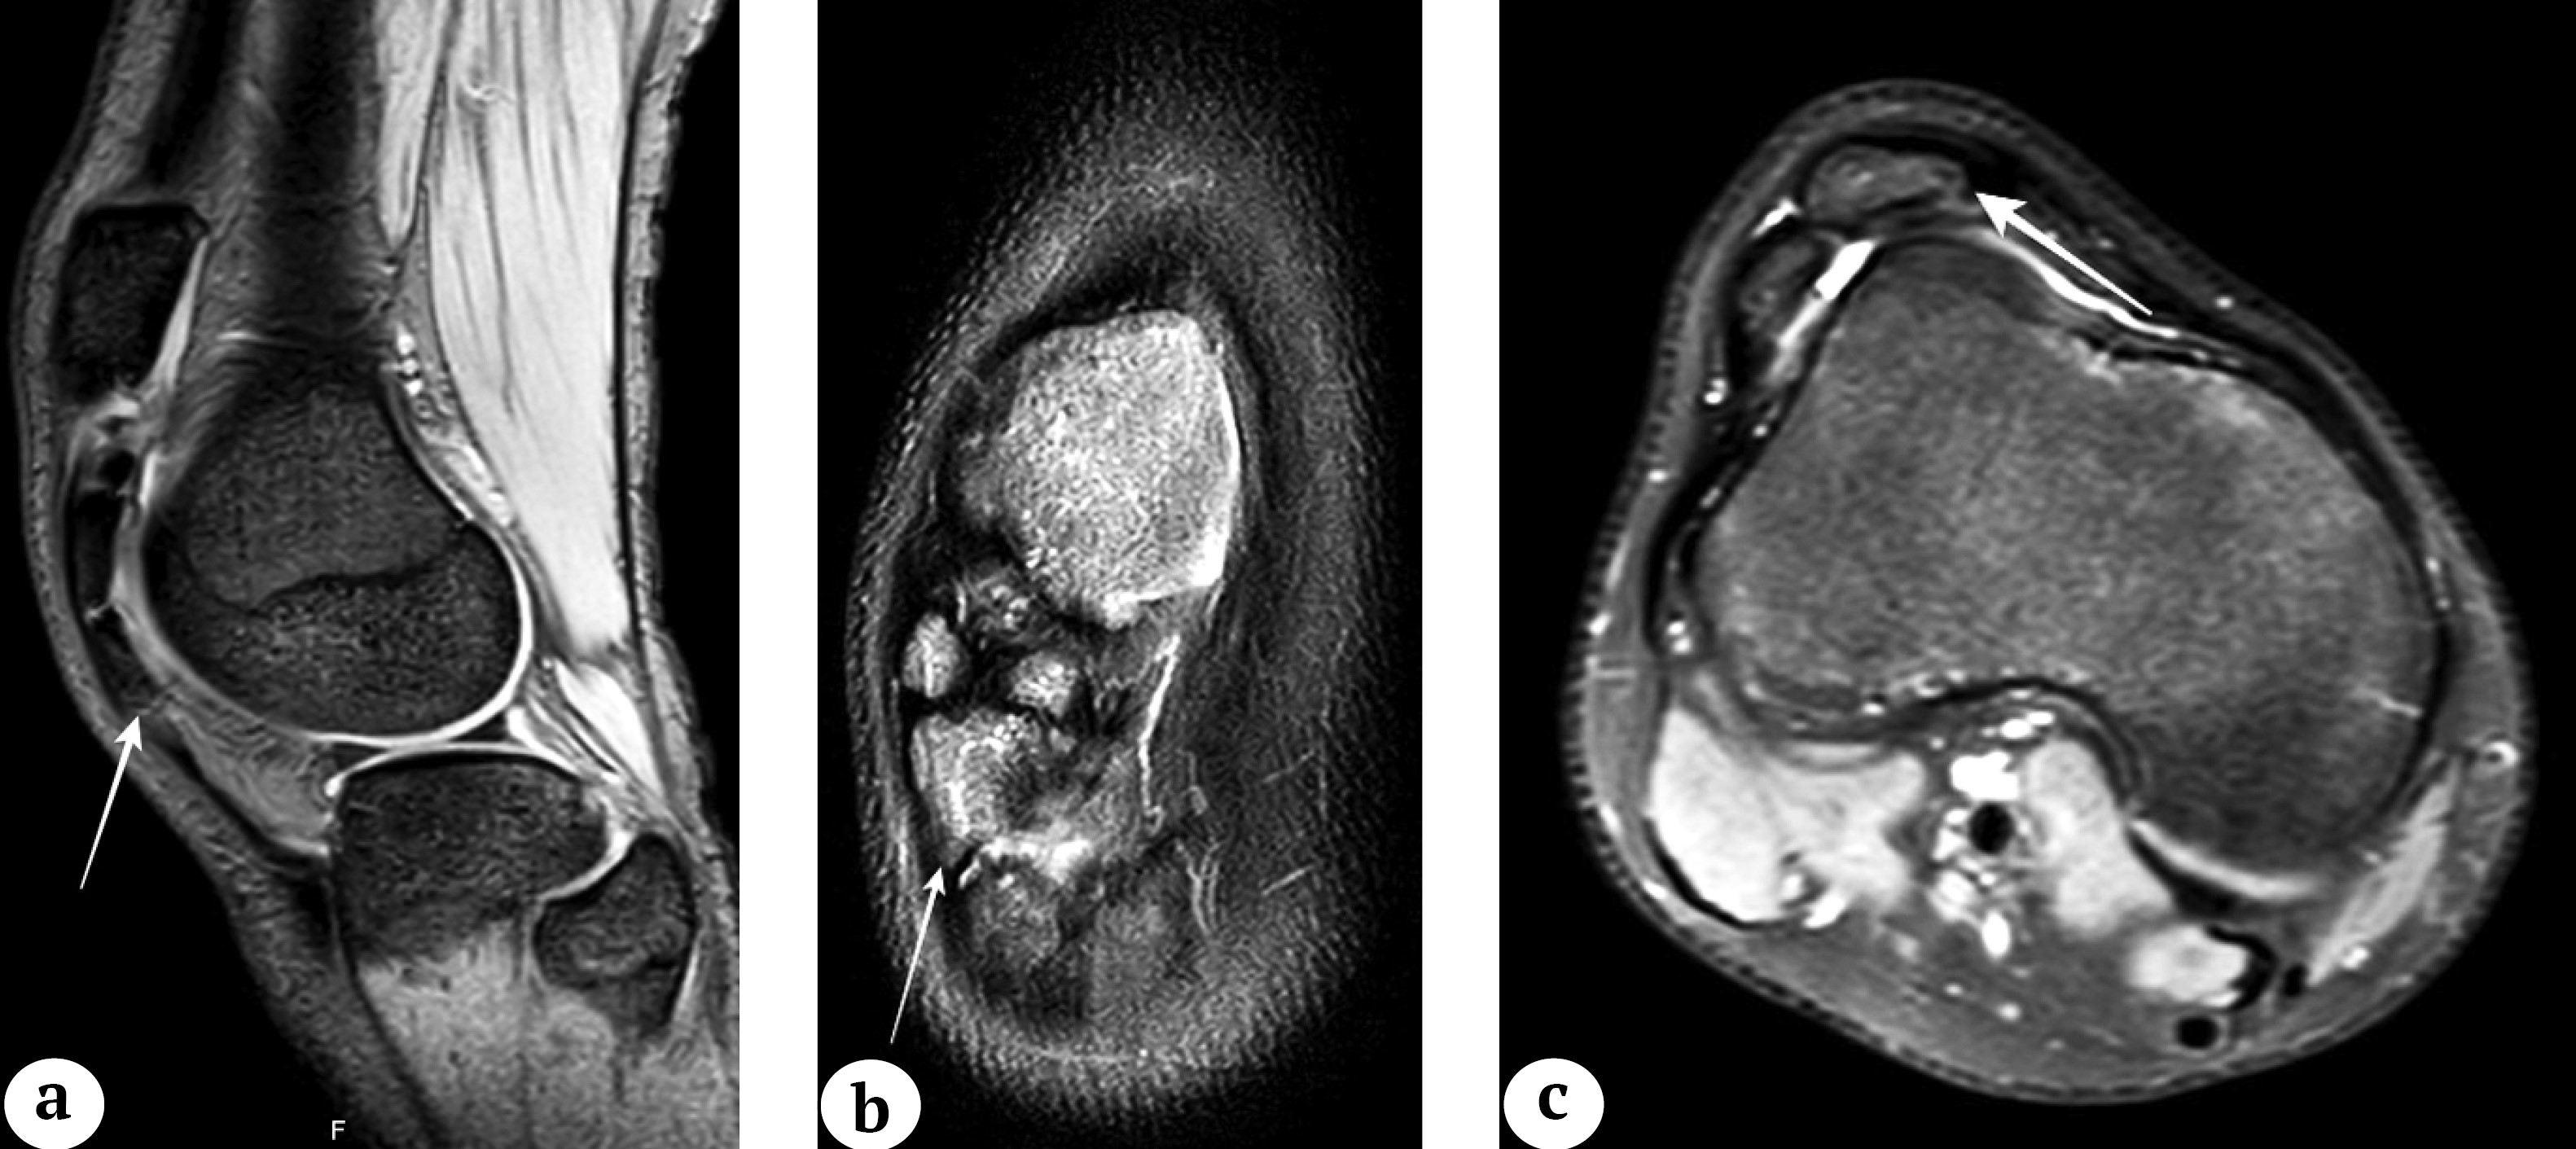

По данным МРТ в проекции связки на участке между бугристостью большеберцовой кости и надколенником определялись патологические образования костной плотности, при этом иногда сама связка между физиологической точкой фиксации и оссификатом не дифференцировалась (рис. 2). У трех пациентов по данным МРТ определялись признаки синовита коленного сустава.

Рис. 2. МРТ коленного сустава у детей с оссификацией связки надколенника (сагиттальная, фронтальная и аксиальная проекции): а — T2 режим (пациент 1), картина оссификата в проекции связки надколенника (обозначен стрелкой); b — T2 режим (пациент 4), многофрагментарный оссификат связки надколенника (обозначен стрелкой); c — T2 режим (пациент 2), срез на уровне наиболее широкой части оссификата (обозначен стрелкой), распространяющегося на всю ширину связки надколенника

Figure 2. MRI of the knee joint in children with patellar tendon ossification (sagittal, frontal and axial views): a — T2-weighted imaging (patient 1), ossification in the projection of the patellar tendon (indicated by an arrow); b — T2WI (patient 4), multifragmental patellar tendon ossification (indicated by an arrow); c — T2WI (patient 2), the cut at the level of the widest part of the ossification (indicated by an arrow), extending over the entire patellar tendon width